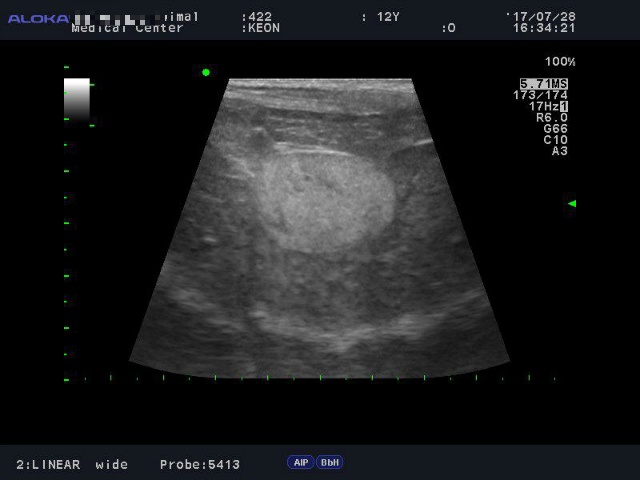

<7월28일> 다시 원점..도로아미타불입니다. 다시봐도 속상하네요 (근데 이게 담낭이 맞긴 한건가..급혼란..)

어제받은 초음파사진들은 몇장 안되니 그냥 다 올려볼게요